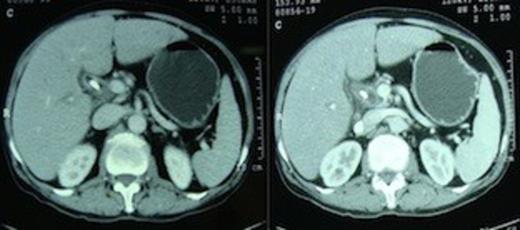

Patient was counseled about the development of diabetes after pancreaticoduodenectomy, which for him would entail removal of the entire pancreas. At surgery, there was no dissemination, a 2×1 cm mass was felt in the region of ampulla. On opening the lesser sac the portal vein was lying bare and the pancreatic neck, body and tail were absent (figure 3).

Operative picture showing the bare portal vein with absent neck, body and tail of pancreas.